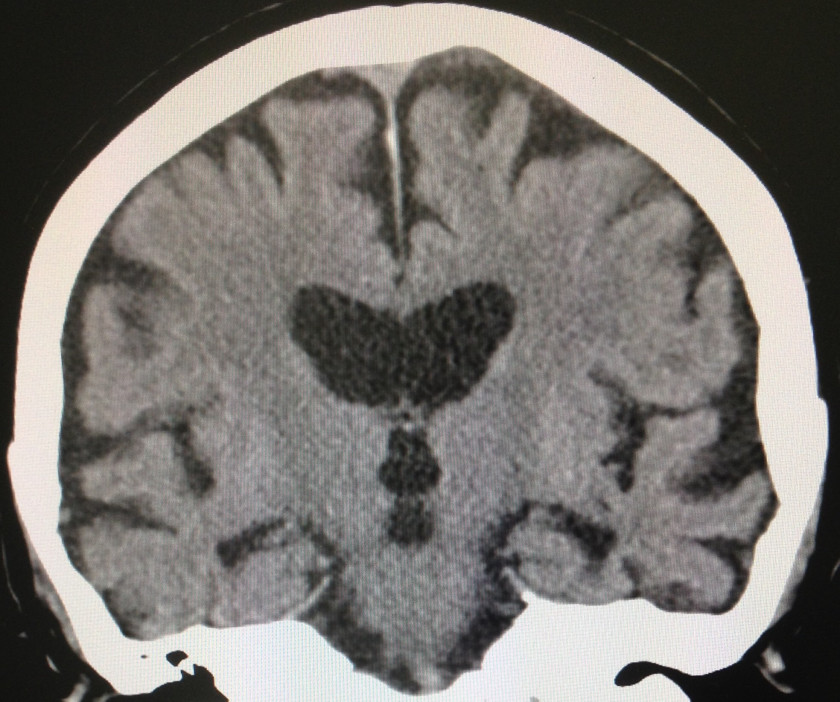

2017/04/05 超一流病院での診断は・・・

超一流病院での診断は・・・この症例は他医療機関の尽力のお蔭で、たくさんの情報を集めることができました。超一流病院での診断は『進行性核上性麻痺(PSP)と正常圧水頭症の合併症例』😂

最初に家族から聞いた時点で、どれも違うな・・・、0点‼️

そうです、最近大流行の・・・『神経変性疾患診断中毒症候群😂』変性疾患の病名を付けないと気が済まない病的医者を受診したら最後ですね😱

MRIの矢状断は何故か良くなかったんで、水平断を出しましたが、これでもOKでしょう。PSPも9亜型ありますが、そもそも、この症例には何ら特徴的な臨床症状が無かったんです。じゃ〜、正常圧水頭症の方は❓・・・否定されました。この冠状断はまた😂

超一流病院での診断は・・・この症例は他医療機関の尽力のお蔭で、たくさんの情報を集めることができました。超一流病院での診断は『進行性核上性麻痺(PSP)と正常圧水頭症の合併症例』😂最初に家族から聞いた時点で、どれも違うな・・・、0点‼️